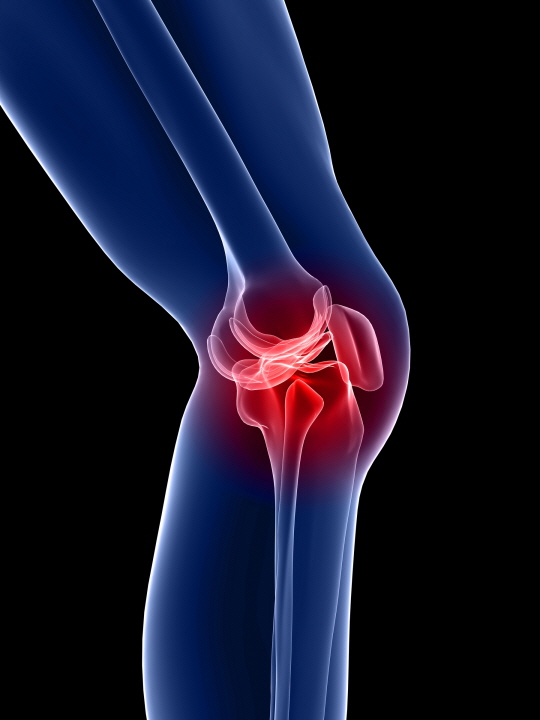

무릎의 연골도 대부분 관절과 동일하게 뼈를 매끄럽고 마찰이 덜가게 생성해 주는 미끄러운 연골 층으로 둘러 축적되어 있어요. 뿐 아니라, 무릎 중앙에는 부가적인 충격 흡수를 전달하는 반월상 연골이라고 하는 두 개의 고무질 반원형 연골 조각이 있어요.

무릎 연골 증상 아니면 무릎 연골 찢어짐은 전문적인 말로 무릎 반월상 연골판 파열이라고요. 반월상 연골은 우리가 무릎을 이용하는 즉 걷거나 뛰거나 점프한 경우 혹은 등때문에 충격을 흡수시켜주는 역할을 해요.

다른 관절과는 차이나게 충격을 잘 흡수해주기 위해 탄력성을 가진 섬유 연골 구조로 되어있어요. 우리가 평상시 과도한 운동을 한 경우 혹은 무릎을 풍부하게 쓰는 행동을 한다면 무릎관절에 3배의 힘이 전해진다고 해요. 그리고 외부로부터 충격을 섭취한다던지 큰 힘을 쓰게 될 경우 무릎 연골 찢어짐때문에 통증이 유발되게 되는 거에요.